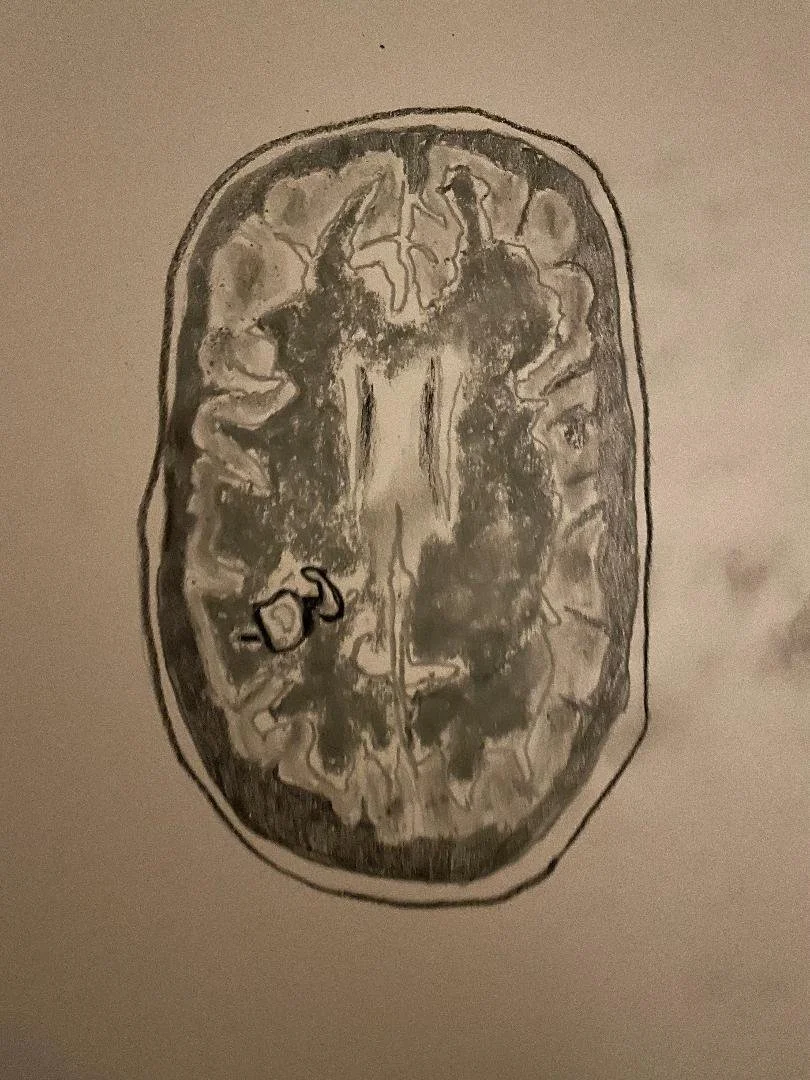

Herpes simplex encephalitis